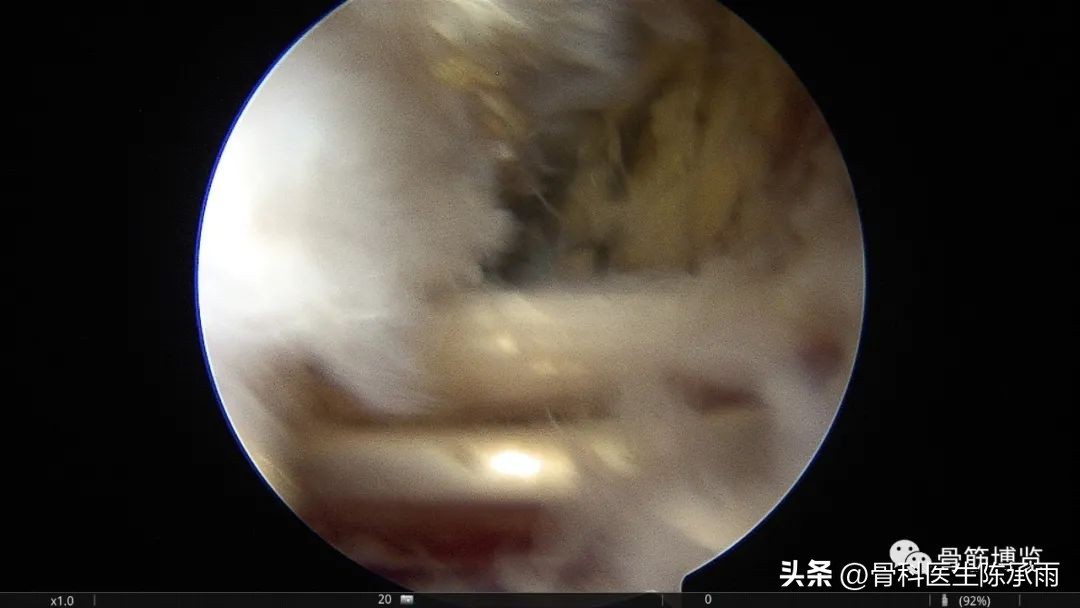

腓肠肌内侧头及半膜肌之间为囊肿内口,显露充分,囊肿内壁大部分切除

探查外侧半月板

镜下囊肿切除∶镜头进入后间室,膝关节放置"4"字位,探针探查腘窝囊肿与关节腔的交通口,通常位于腘窝囊肿前方后内侧关节囊皱襞上。通过后内侧入路用刨削器将后内侧关节囊皱襞清除,充分地扩大腓肠肌内侧头与半膜肌之间的交通口,并清理增生的束带组织,使得腘窝囊肿和关节腔之间的滑囊液可以双向流动。充分显露腓肠肌内侧头,可于腓肠肌内侧头与半膜肌之间暴露出腘窝囊肿,通过关节镜对腘窝囊肿进行关节腔内引流。将刨削器和关节镜伸入囊肿内部清理囊腔,屈曲膝关节至"4"字位,从外侧挤压囊肿位置,从而使囊壁更易切除。也可以在手术前向腘窝囊肿内注射亚甲蓝 2ml,可在镜下更好显示囊肿,完全切除亚甲蓝染色的囊壁、囊内分割部分和可能的多发性囊肿的囊壁。

关节镜手术视野清楚,能充分切除囊肿内壁及与关节腔内的沟通,因此比开放手术更微创、切除更彻底、复发率更低,还能处理关节内伴随疾病,是近年来推荐的首选手术方法,但关节镜有一定的学习曲线。手术的关键是找到腓肠肌内侧头,沿该结构后内侧暴露出半膜肌,在腓肠肌内侧头与半膜肌之间就是腘窝囊肿。术前亚甲蓝注射有助于关节镜找到腘窝囊肿并切除囊壁,是一种比较好的方法。